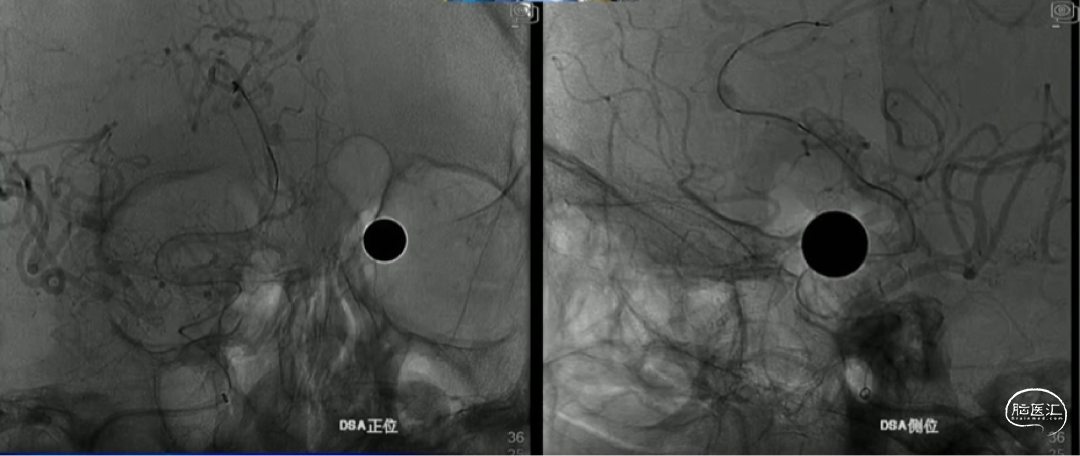

如意完全释放

支架整体释放后,贴壁良好,打开良好,无需再次按摩支架贴壁,故上高心玮DMC21微导管,回收带镍钛球囊的输送导丝。

术后即刻造影,动脉瘤滞留明显,载瘤动脉管腔通畅无狭窄,支架贴壁理想。

“如意”血流导向密网支架很好打开,镍钛小球助力支架更好的二次打开,支架释放中就能达到自膨打开,无需按摩,是一款各方面性能都不错的支架。